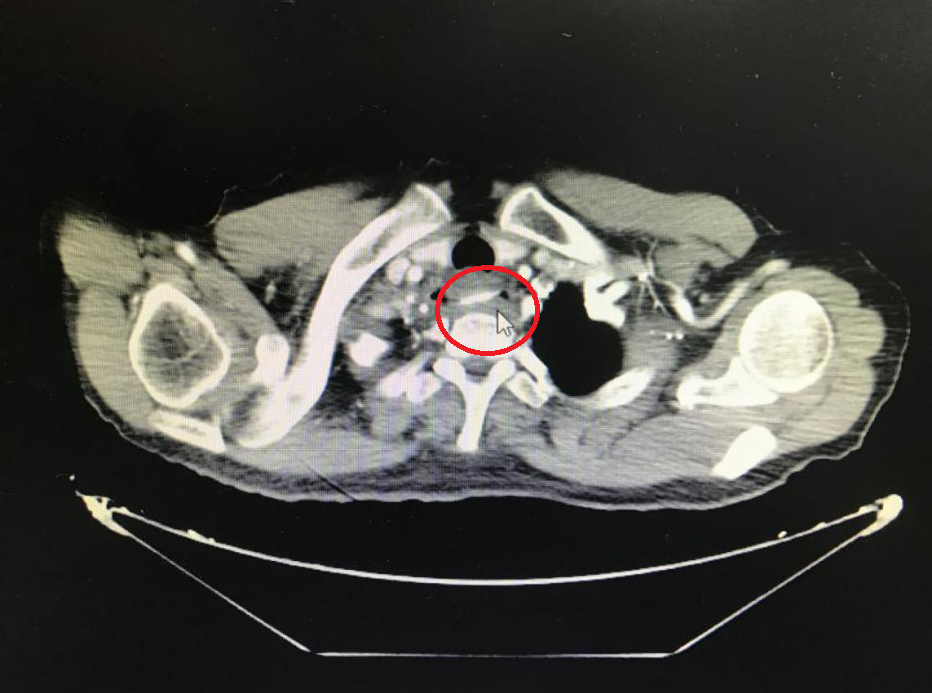

纵然专家见多识广,看到鱼刺也连连惊叹:“圆月弯刀状的鱼刺长达8厘米,真不知道是怎么咽下去的!”

检查发现,鱼刺像一把圆月弯刀,横插在食管和胸主动脉附近,已刺穿食管壁。如果盲目拔出,必定会形成主动脉破口。胸主动脉是人体最粗大的动脉血管,压力很高。一旦形成破口,出血犹如“大坝决堤”一般,难有抢救机会。

手术方案立即调整。胸外科黄杰教授团队接力上台。果然,鱼刺穿出食管,几乎整个扎进主动脉内,仅在外露出3毫米的刺尖。